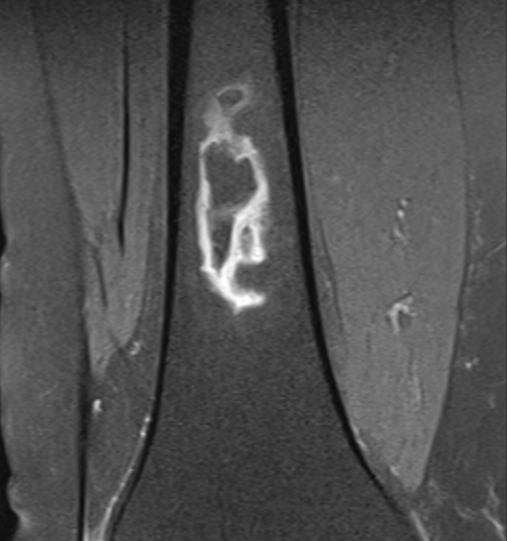

Bone infarct geographic appearance